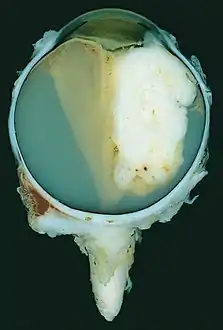

| A pathology specimen of a retinoblastoma tumor from an enucleated eye of a 3-year-old female | |

Gross and microscopic appearances of retinoblastoma are identical in both hereditary and sporadic types. Macroscopically, viable tumor cells are found near blood vessels, while zones of necrosis are found in relatively avascular areas. Microscopically, both undifferentiated and differentiated elements may be present. Undifferentiated elements appear as collections of small, round cells with hyperchromatic nuclei; differentiated elements include Flexner-Wintersteiner rosettes, Homer Wright rosettes,[29] and fleurettes from photoreceptor differentiation.[30]

Large exophytic white tumor with foci of calcification producing total exudative retinal detachment